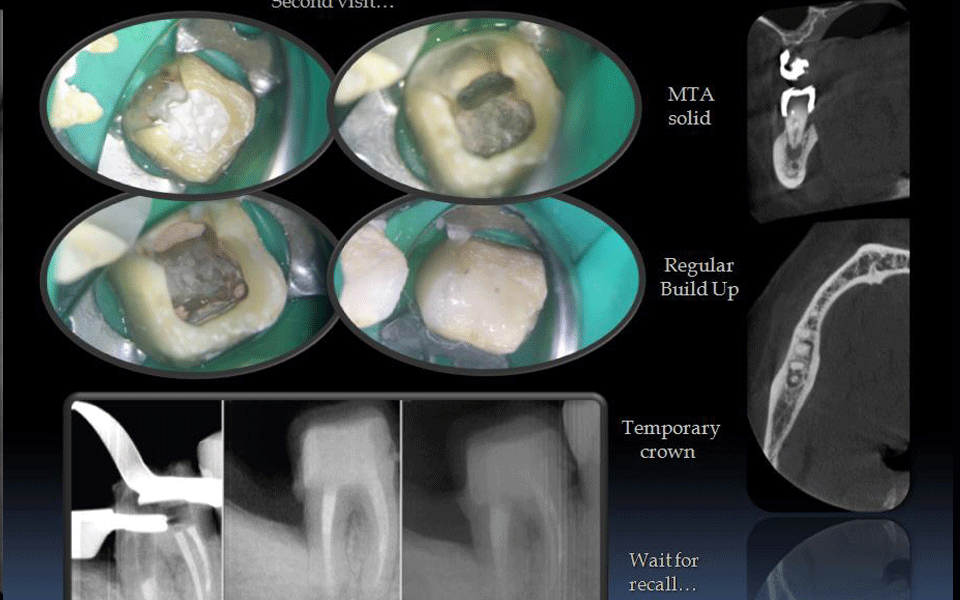

Перфорации

если случились перфорации (проколы) во время лечения зубного канала, нарушилась герметичность зуба, обнаружить и закрыть перфорации поможет микроскоп.